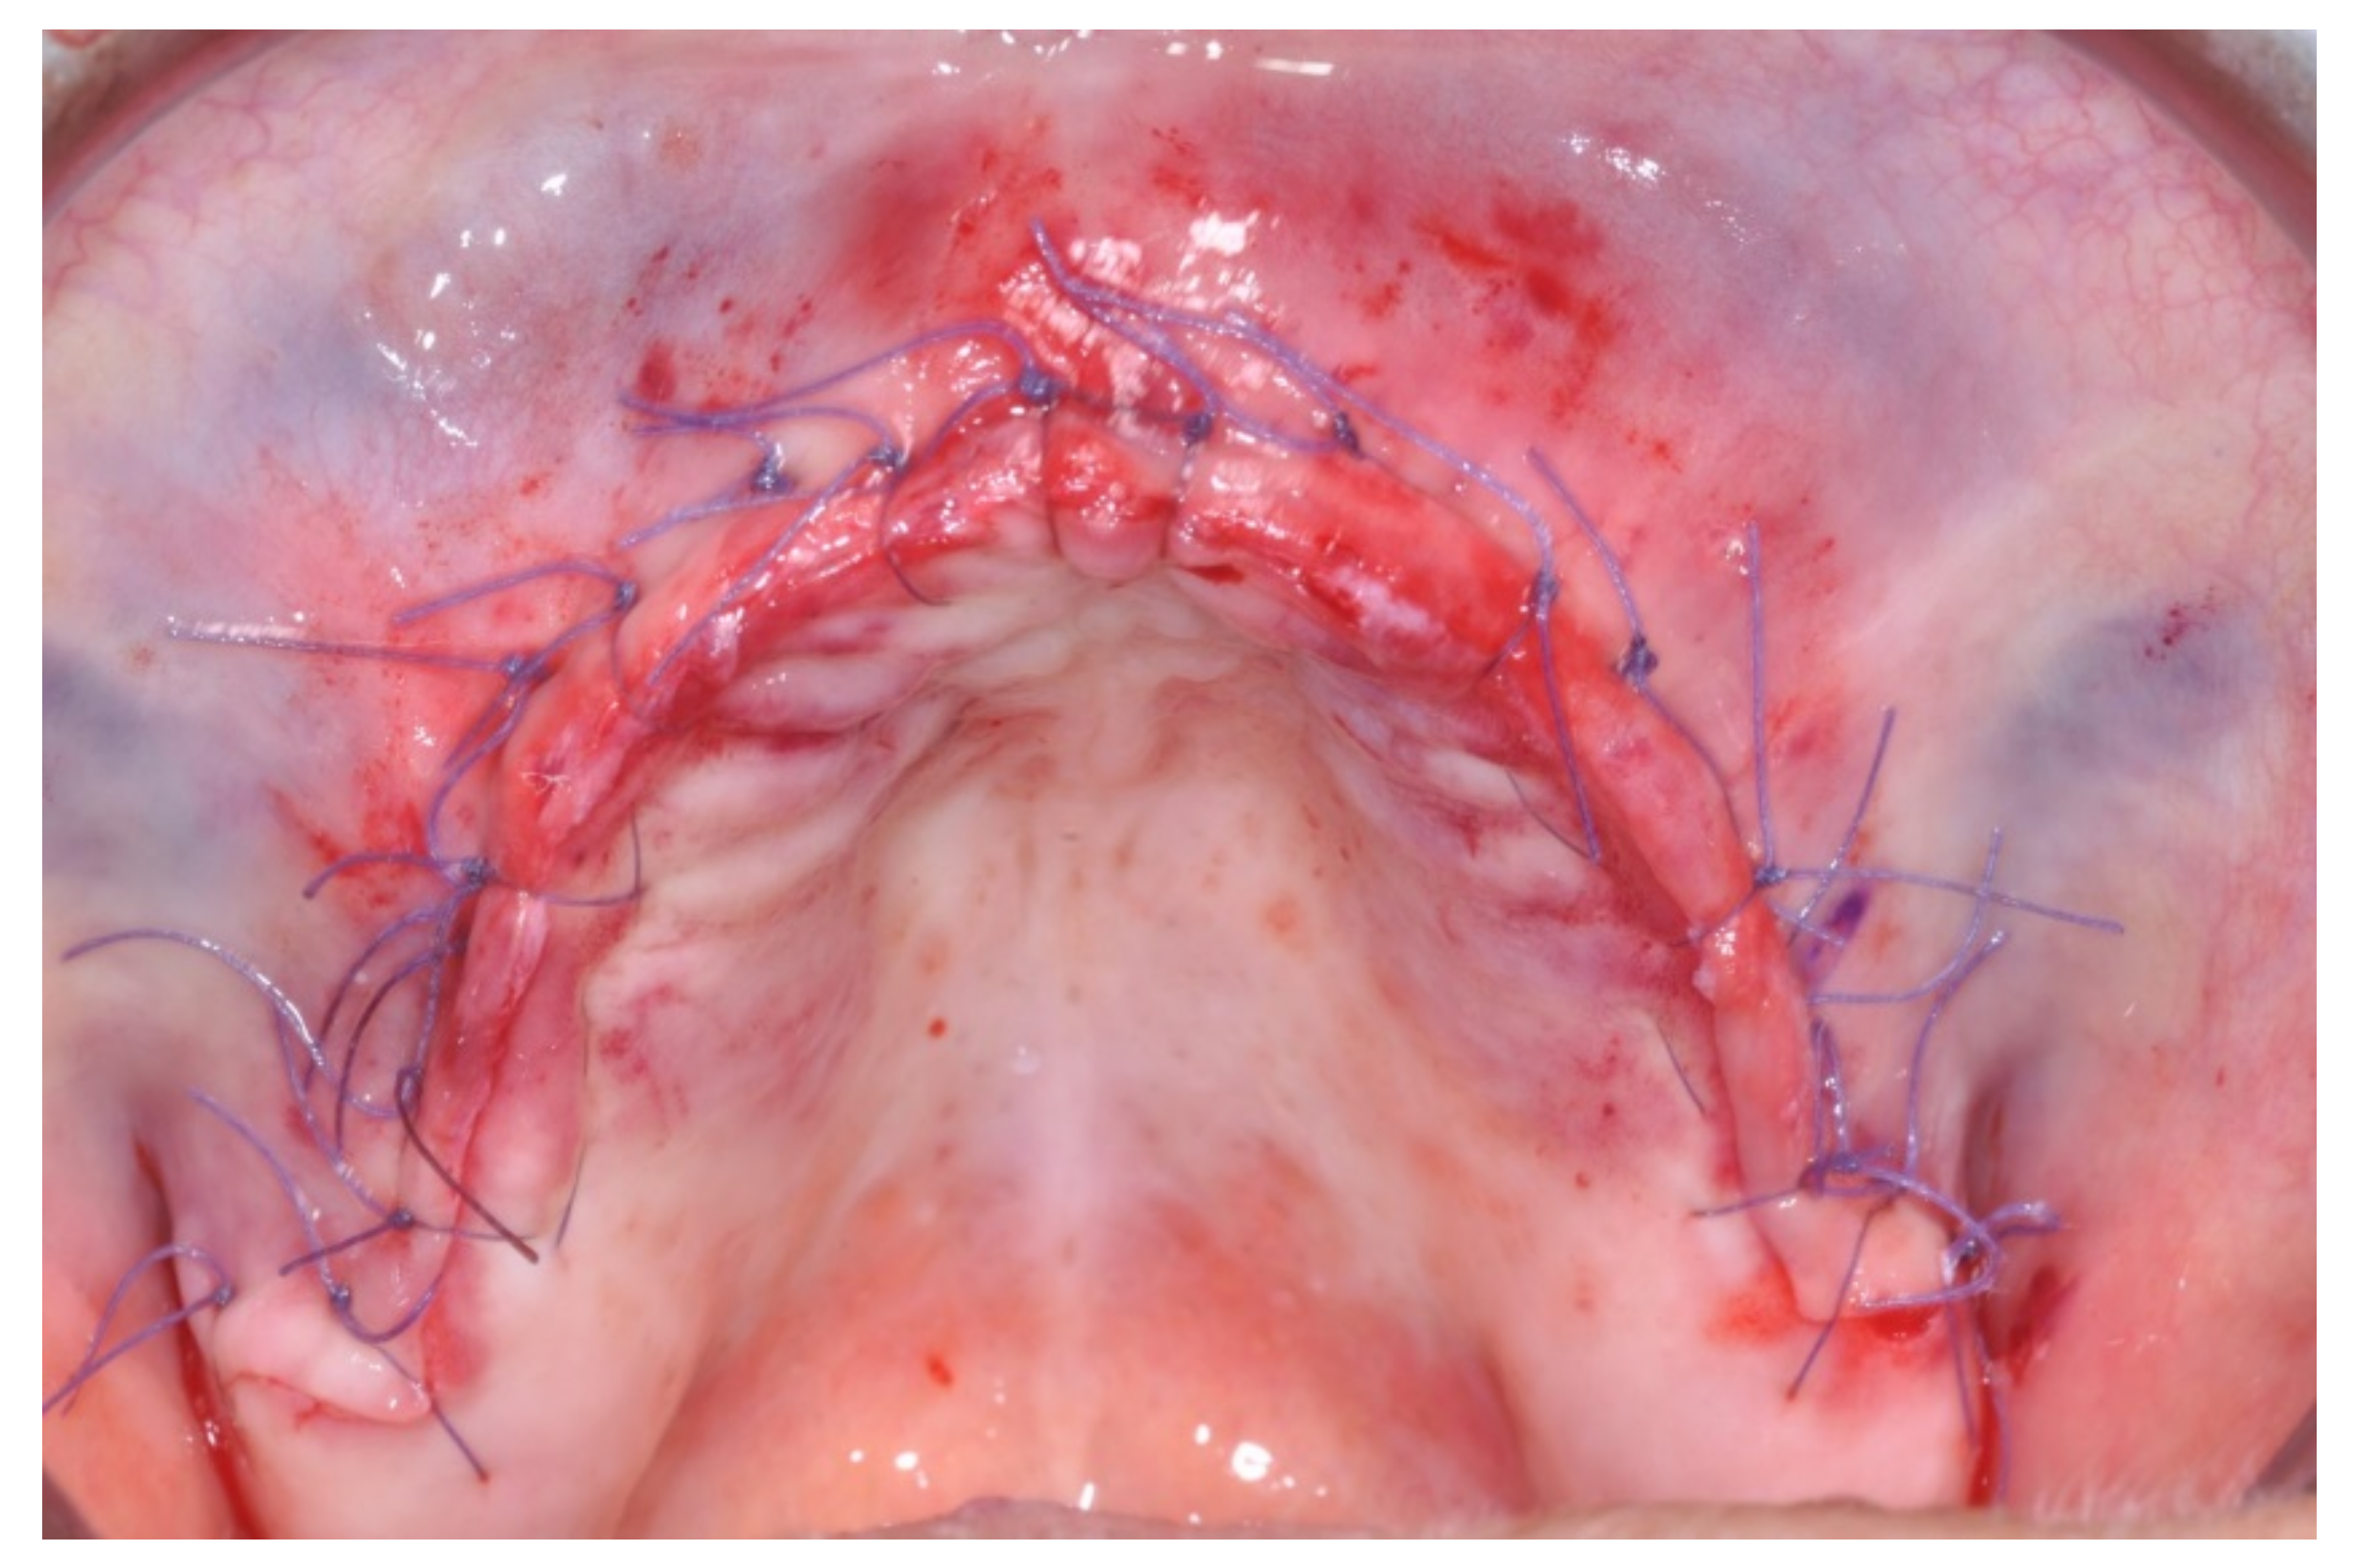

Resorbable sutures (Vicryl 6-0 SH1 needle of 17 mm 1/2c; Ethicon, New Brunswick, NJ, USA) were placed, alternating between single sutures and horizontal mattrass sutures (Figure 13).

Figure 13. After suturing.